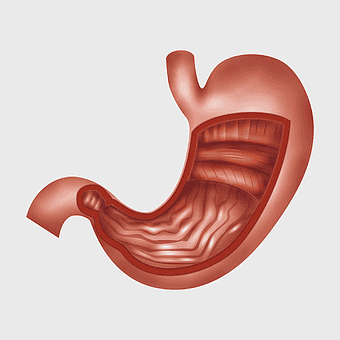

human stomach anatomy, gastrointestinal tract illustration, digestive system organ, abdominal cavity viscus, internal organ diagram, medical biology graphic, human body internal structure -

human digestive system anatomy, gastrointestinal tract illustration, stomach muscular layer, abdominal organ diagram, digestive health education, medical biology study, internal human body structures -

stomach illustration, full stomach anatomy, abdominal organ depiction, human digestive system, gastroenterology graphics, medical illustration artwork, digestive health visual -

human stomach anatomy, gastrointestinal tract illustration, small intestine diagram, peptic ulcer disease, digestive system health, internal organ function, pink medical graphic -